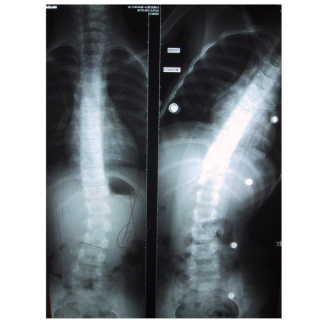

Dos / rachis / thorax Corsets de traitement scoliose Corset nocturne en hyper-correction dit de "Charleston"

• Scoliose idiopathique chez l’adolescent

• Scoliose à courbure simple ou double

- Courbure cervico-thoracique

- Courbure thoracique haute

- L'enfant est placé en inflexions latérales, en hypercorrection

- Cette correction à «mi-temps est parfois suffisante pour contenir avec succès une déviation scoliotique

- Peut être utilisé en complément d’un corset C.T.M.